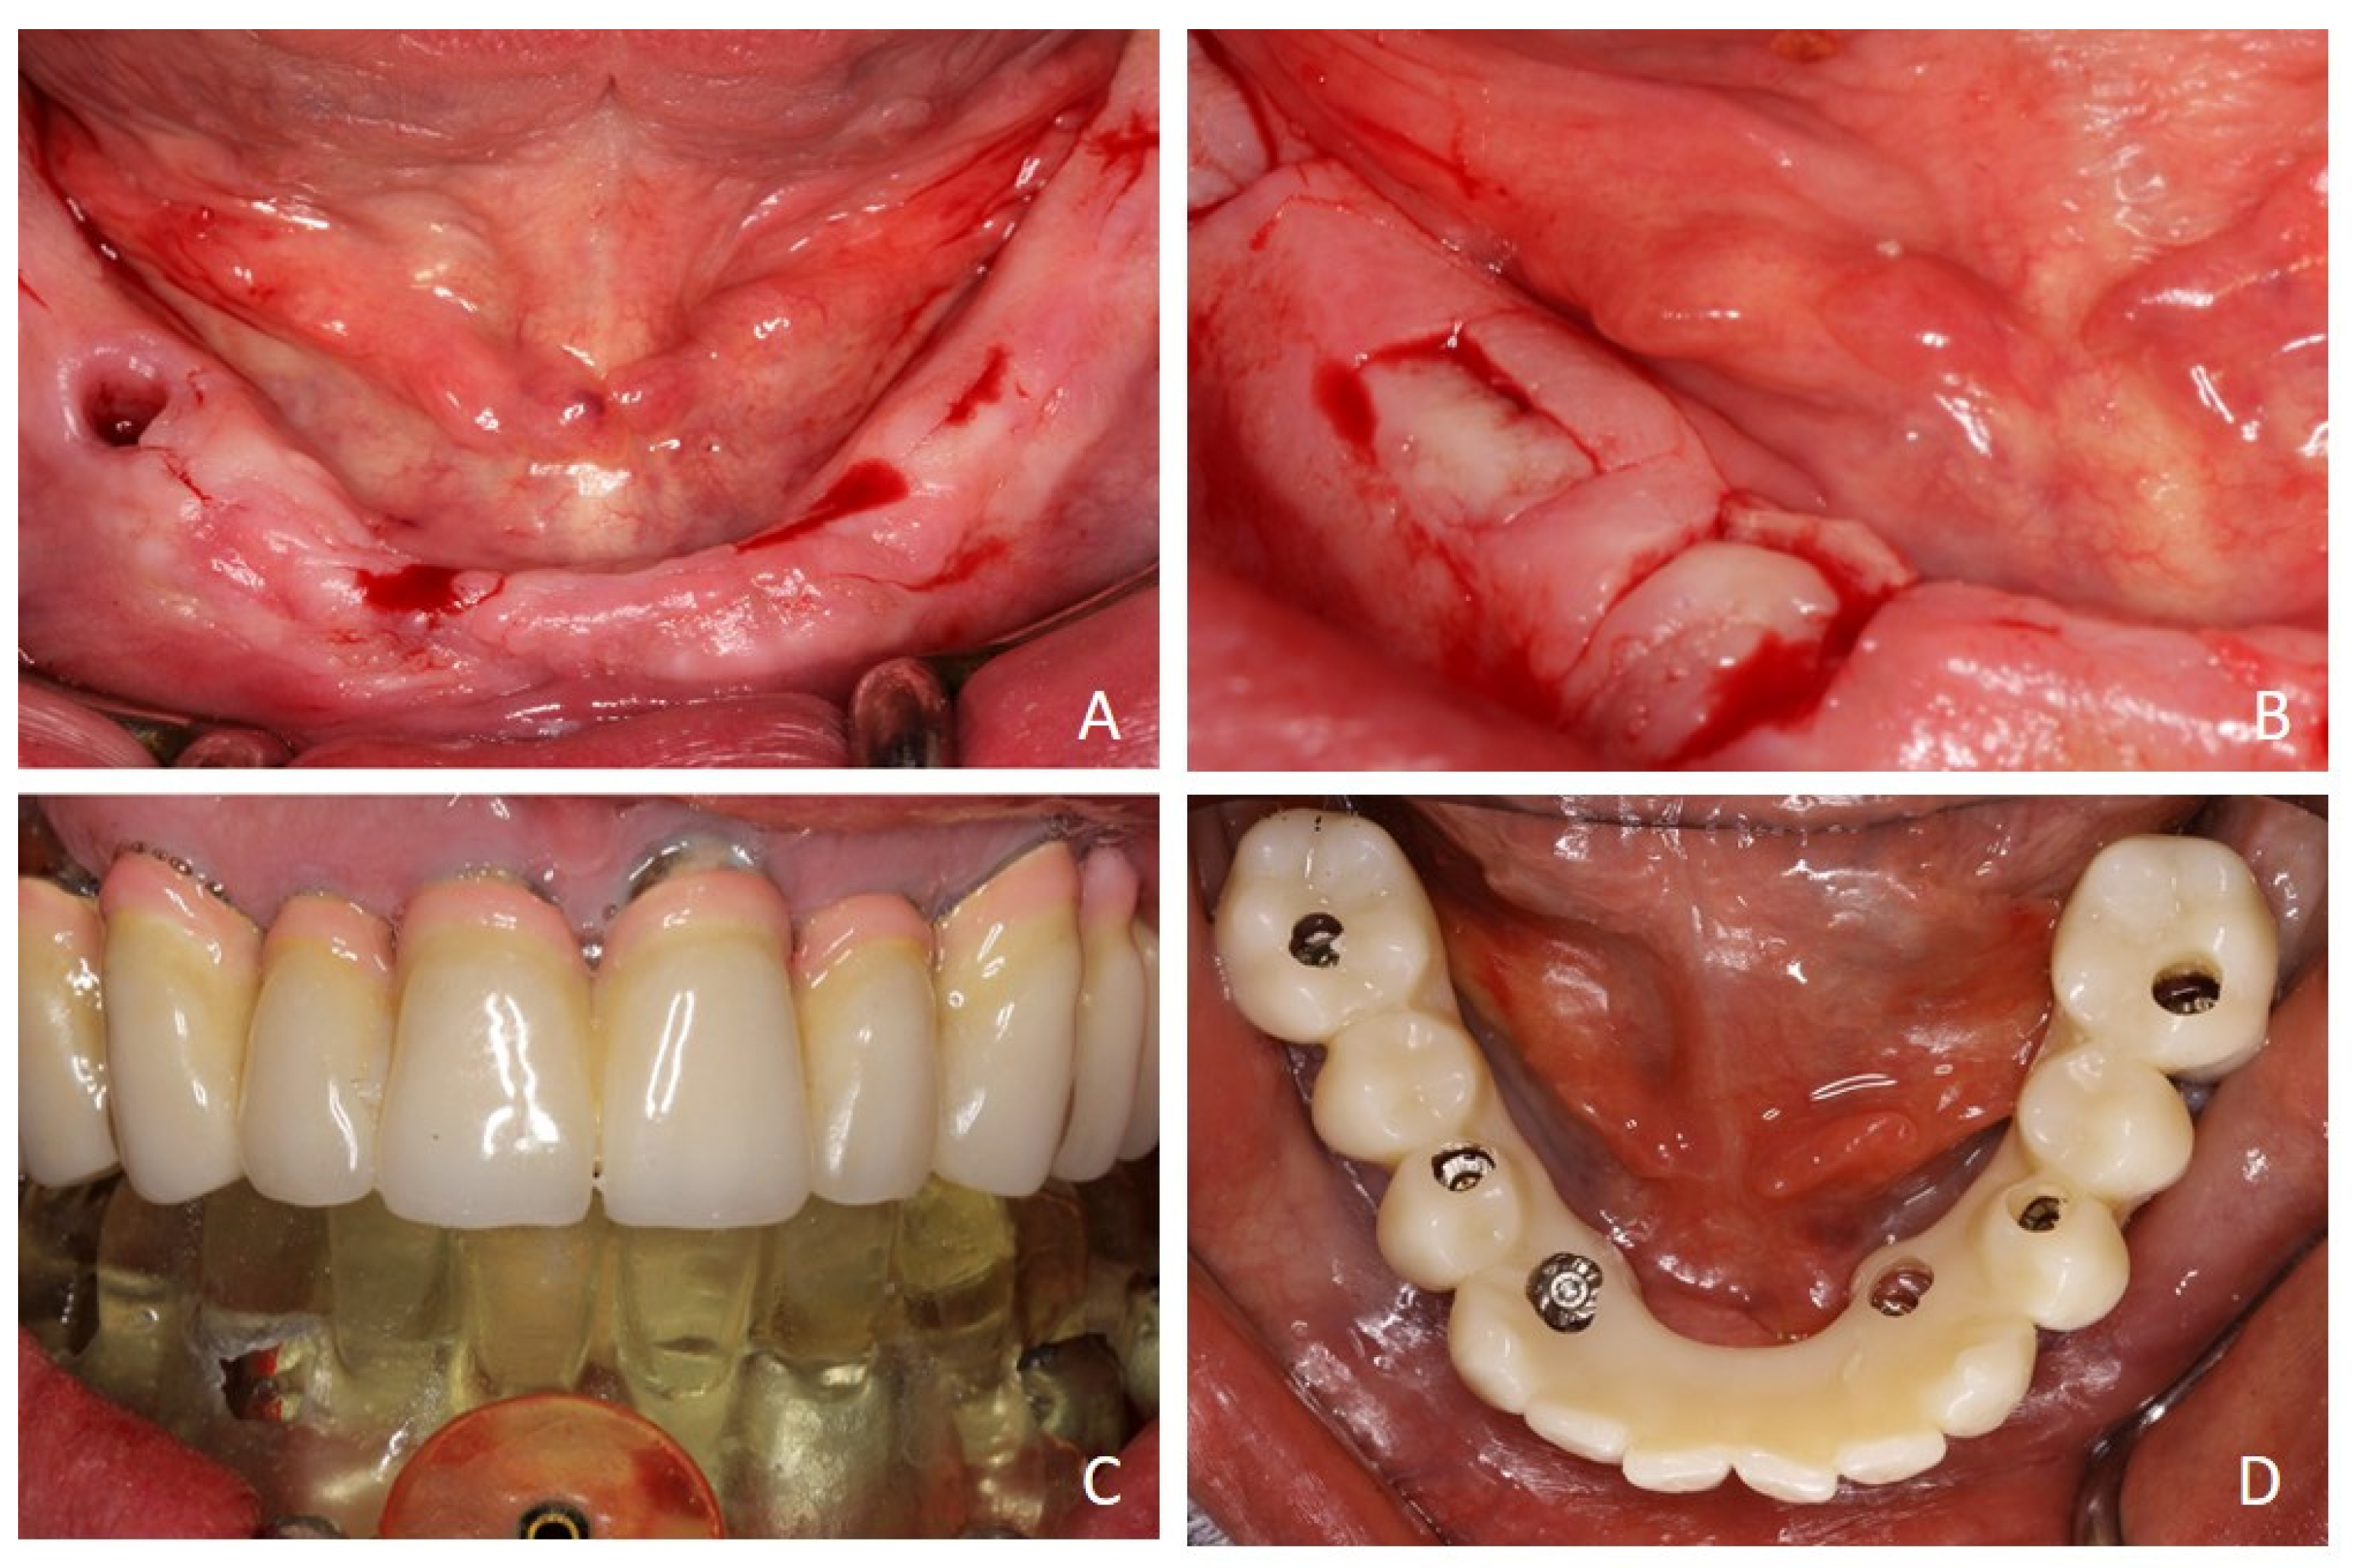

2. Case Report

3. Surgical Strategy